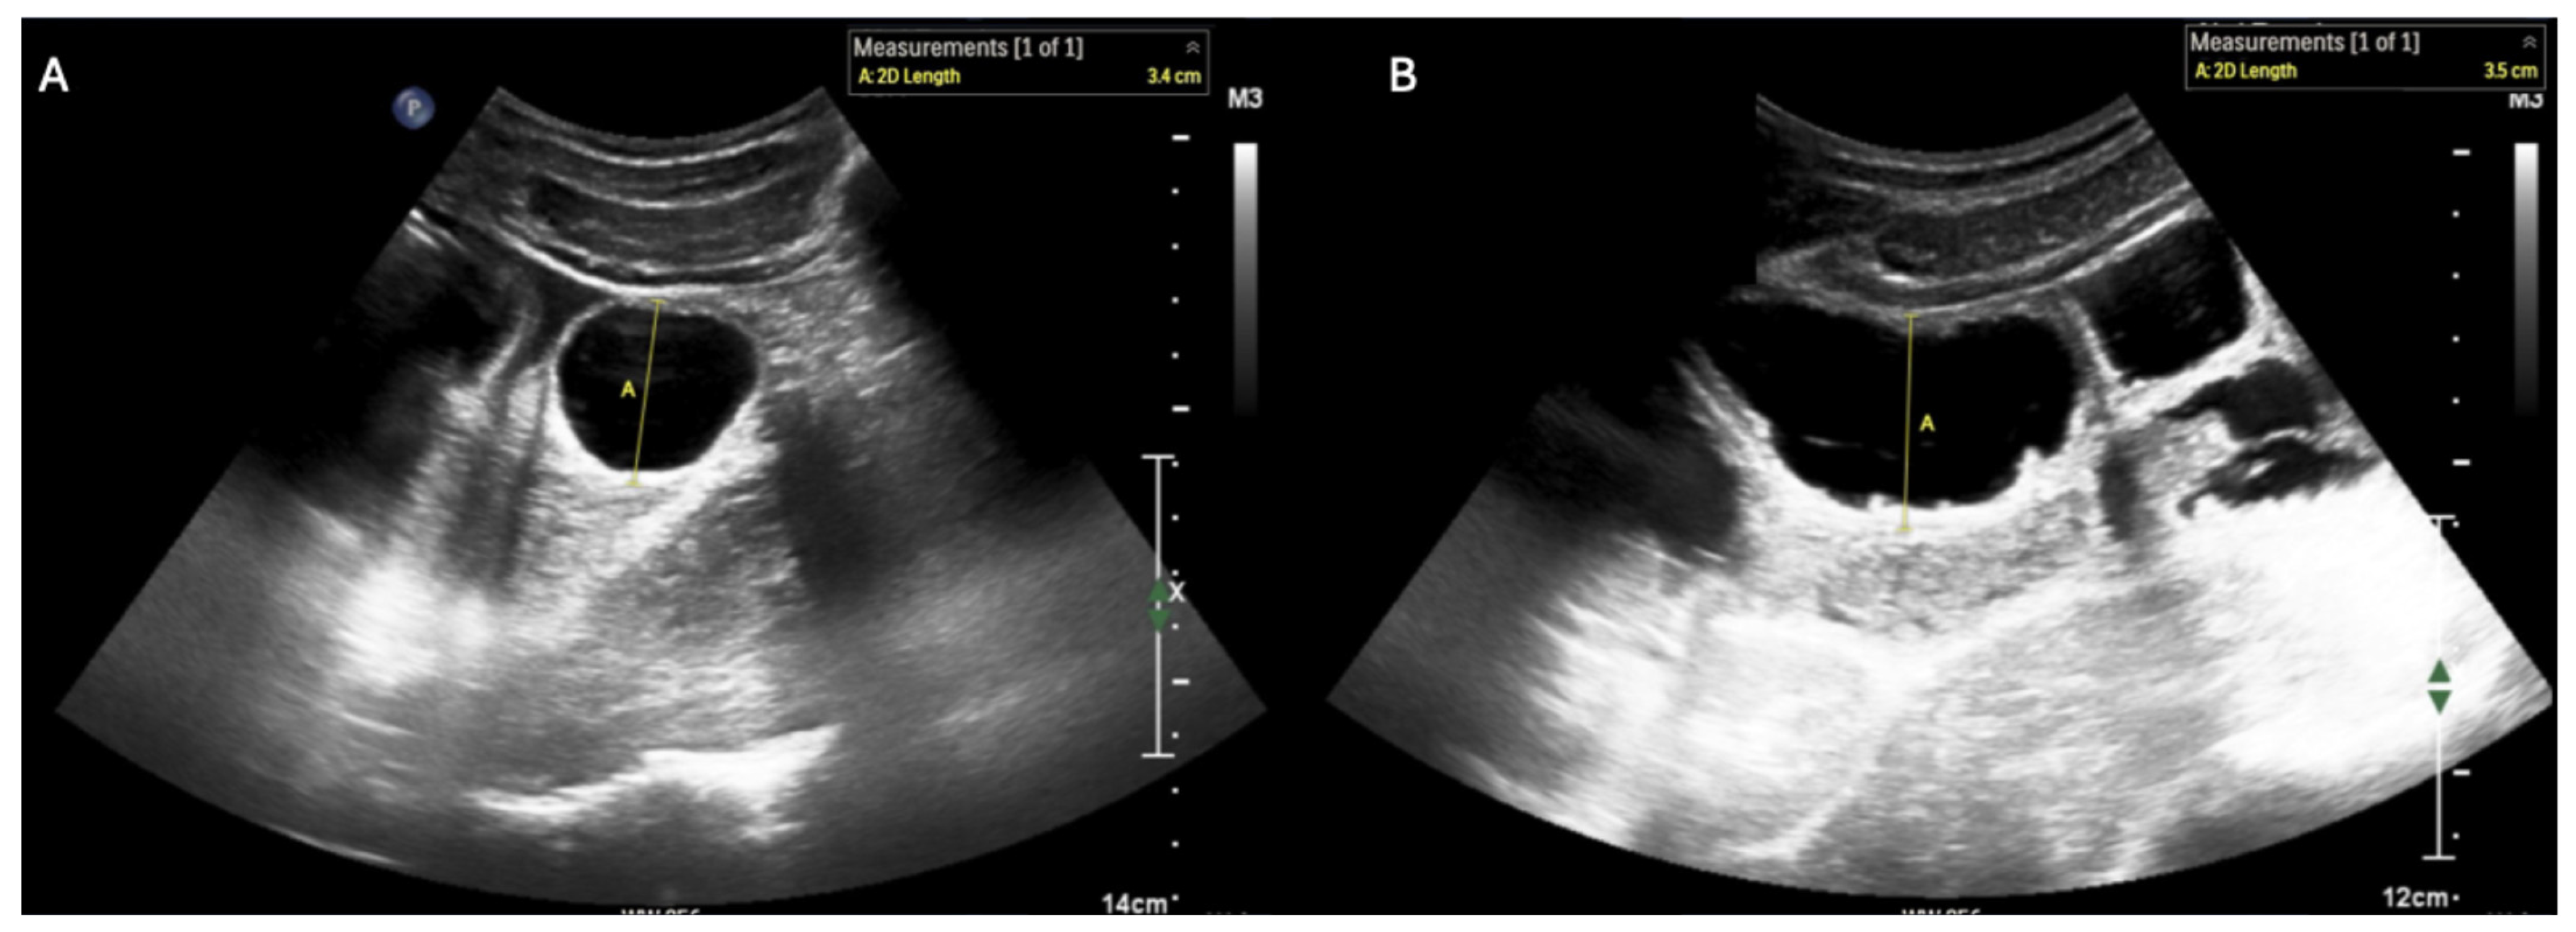

- Ogata, M.; Imai, S.; Hosotani, R.; Aoyama, H.; Hayashi, M.; Ishikawa, T. Abdominal sonography for the diagnosis of large bowel obstruction. Surg. Today 1994, 24, 791–794. [Google Scholar] [CrossRef]